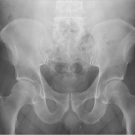

A 63-year-old man presented to his primary care physician’s clinic with left hip pain after sustaining a fall while roller skating 2 years earlier.